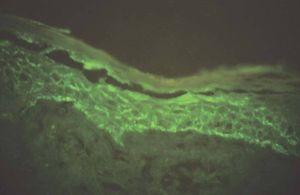

La técnica se basa en fijar la biopsia en la solución fijadora (tabla 1) en la que puede mantenerse hasta 10 días, y probablemente más, hasta su procesado. Tiempo suficiente para remitirlo a cualquier laboratorio. Antes de su congelación la muestra debe lavarse tres veces durante 10 minutos en un buffer (tabla 2) tras lo cual puede congelarse y procesarse de la forma habitual para inmunofluorecencia. La tabla 3 recoge un resumen del procedimiento y la figura 1 muestra un ejemplo positivo de una biopsia procesada de esta forma.

Figura 1. Inmunofluorescencia de una biopsia de pénfigo foliáceo que fue remitida al hospital de referencia con el medio Michel.